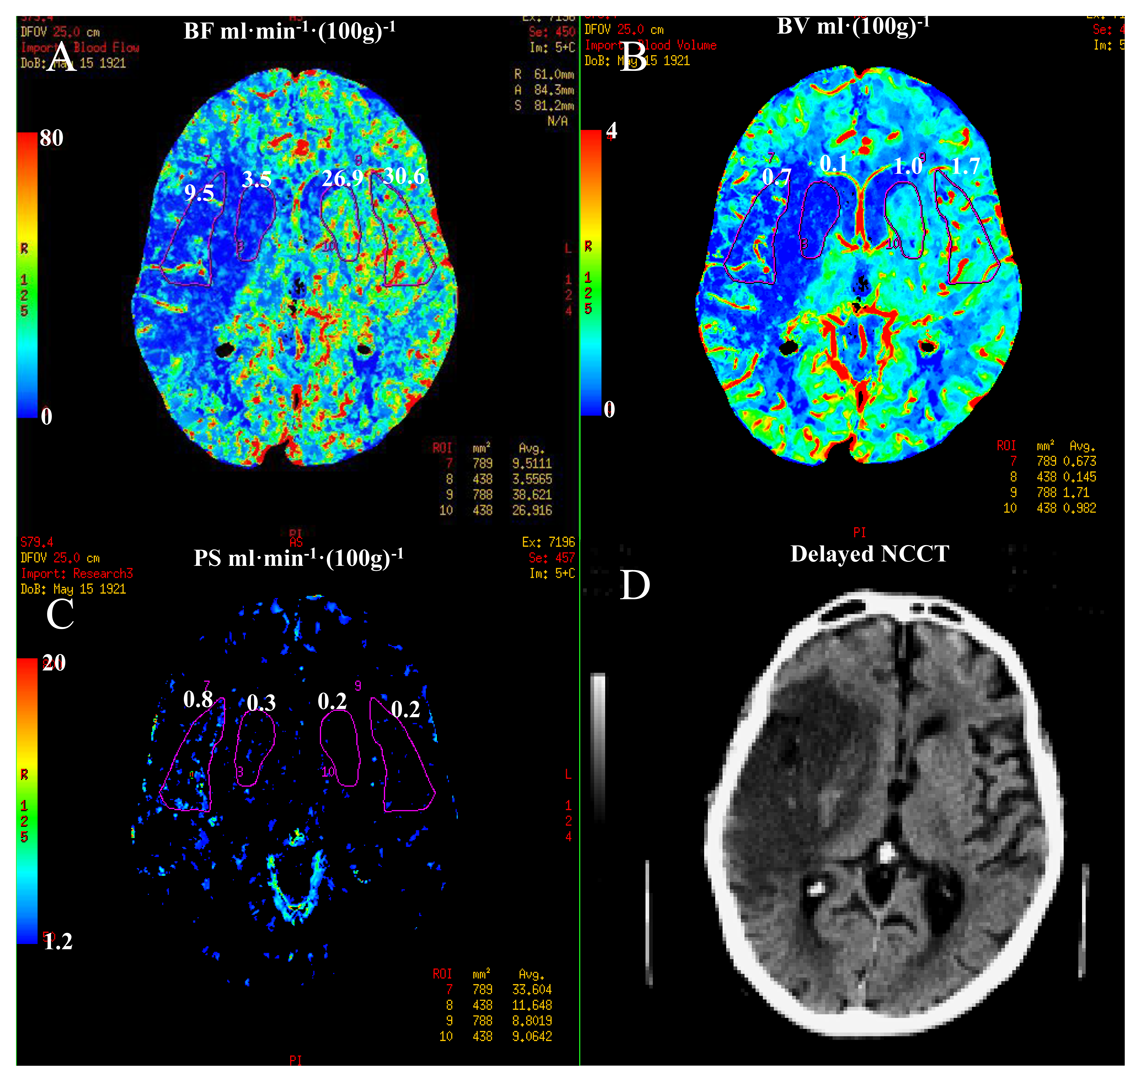

Techniques capable of characterizing BBB integrity may prove particularly valuable because there is a credible association between BBB disruption and risk of hemorrhagic transformation with thrombolytic therapy. For the assessments of BBB permeability paramagnetic contrast agent is administered intravenously using a bolus injection. With an intact blood brain barrier the contrast agent passes through the microvasculature of the brain, being contained to the intravascular space. During stroke there are areas of the brain that are associated with BBB breakdown and it is in these areas that the contrast agent can extravasate into the interstitium. There are two methods of detecting BBB breakdown: (1) static T1-weighted MR imaging; and, (2) dynamic contrast enhanced MRI (DCE MRI) [97]. Post contrast T1-weighted MRI is specific for BBB breakdown implying that it is not visualized when the BBB is not dysfunctional but its limitations relate to the infrequency of its detection during the early period after symptom onset and it is relatively insensitive to predicting hemorrhagic transformation (sensitivity 39%) [98,99]. Therefore, post contrast T1-weighted MRI does not have sufficient diagnostic accuracy for routine clinical decision-making. The low sensitivity of post contrast T1 MRI may be partially explained by the failure of contrast arriving to the ischemic during either microvascular or large artery occlusion. The addition of continuous low dose infusion of contrast to the initial bolus dose could improve the sensitivity of post contrast T1-weighted MRI [100]. The downside of this technique is that it requires a long image acquisition, which may be impractical in the context of acute ischemic stroke. The availability, speed and accessibility of CT are the main reasons that CT remains the diagnostic procedure of choice for the treatment of stroke with thrombolysis. CT is capable of generating physiological information about the penumbra. This can be achieved by a 40–50 s DCE or CT perfusion examination. By extending the acquisition time information about BBB integrity or permeability can be obtained (Figure 6) [101].

More research is required in this area but it is hypothesized that dynamic contrast MRI or CT may be useful in the prediction of hemorrhagic transformation in acute ischemic stroke. It has been proposed that measurements of BBB permeability in acute stroke may aid in selecting acute ischemic stroke patients for treatment based on imaging criteria of BBB integrity, avoiding the restrictive eligibility criteria mandated by the time window paradigm. Knight et al. showed that DCE MRI in a rat model of progressive parenchymal enhancement was highly correlated with the presence of hemorrhagic transformation [102,103]. The main potential drawback is that BBB permeability following ischemic stroke is physiologically a highly dynamic process, and therefore, the imaging at one time point may only provide “snapshot” may not be represent the disease process at a later time point[97]. Such techniques have been performed in human subjects, but it is as yet too early to formalize a permeability threshold facilitating treatment allocation.